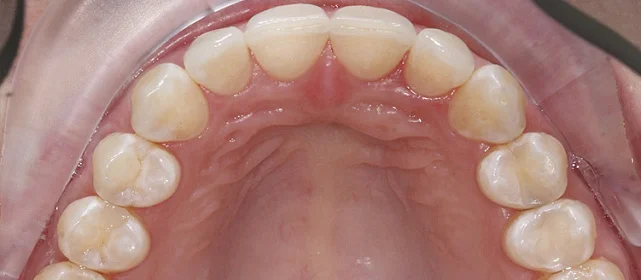

Зубы выровнены, скученность устранена, прикус исправлен, линия смыкания нормализована. Ретейнер установлен на нижнюю челюсть. На верхней ретейнер не ставили — на передних зубах коронки, вместо этого изготовлены ретенционные капы на обе челюсти. Пациентка направлена к ортопеду для замены коронок.

Решение: Поставили элайнеры Click на обе челюсти. Основной набор — 31 капа, плюс два дозаказа: 26 и 7 кап, итого 64. При этом лечение уложилось в 20 месяцев — быстро для такого объёма работы. Расширили дуги, убрали скученность, исправили прикус, выровняли линию смыкания. Ретейнер поставили только на нижнюю челюсть. На верхней от ретейнера отказались сознательно — на передних зубах коронки, и проволока там не ляжет корректно. Вместо этого изготовили ретенционные капы на обе челюсти. Ортопедию — замену старых коронок — пациентка будет проходить у себя в городе.